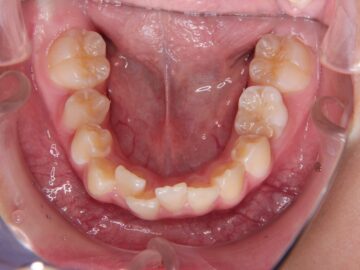

ご相談時

八重歯・歯がガタガタしている